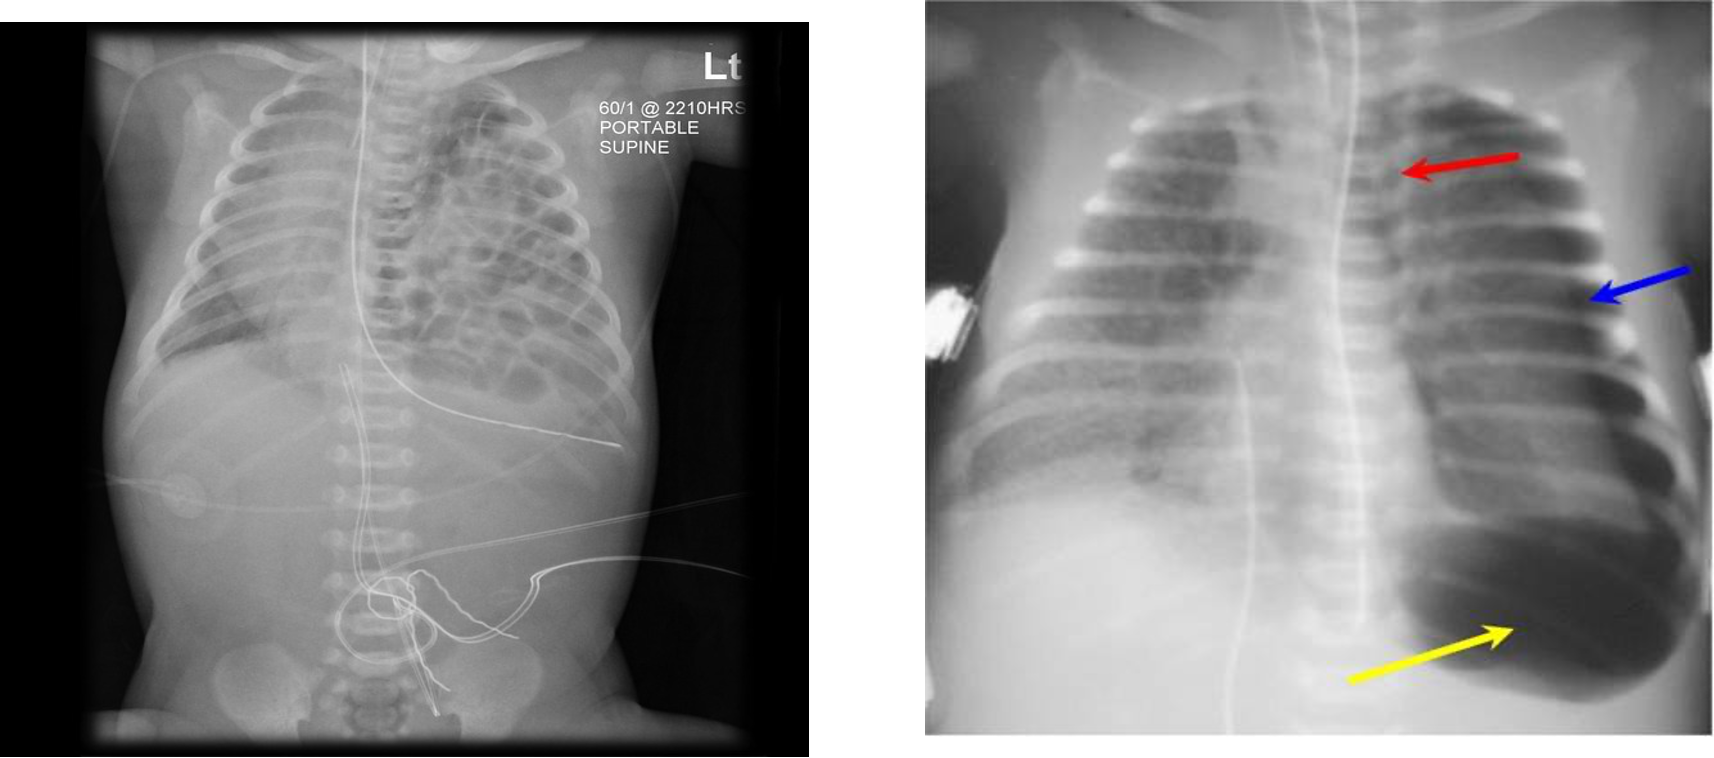

- CXR may suggest lung disease particularly if the findings are asymmetrical.

- If the changes are diffuse and symmetric, i.e., compatible with pulmonary edema or increased PVM, it is difficult to differentiate between primary lung disease or heart disease causing pulmonary edema, e.g., TAPVD with obstruction.

- A chest radiograph: cardiomegaly, narrow mediastinum, and increased pulmonary vasculature. ECG: RAD and RVH

Imaging

- Small to N cardiac silhouette

- Decrease pulmonary vasculature